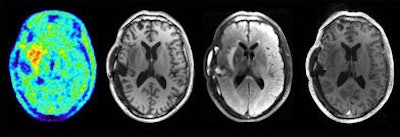

L'image des noyaux gris centraux obtenue à 3 tesla (ci-dessus) est loin de la qualité de l'image obtenue à 9.4 tesla (ci-dessous).

Images du cerveau obtenue par IRM pendant une acquisition TEP: TEP FET, T1, T2 combiné, et T1 après injection de contraste.A l'aide de l'IRM à ultra haut champ et l'imagerie TEP du cerveau "le positon vole dans le champ magnétique, et ses mouvements vont être limités à deux directions, et nous devrions améliorer la résolution de la TEP sans aucun coût supplémentaire".